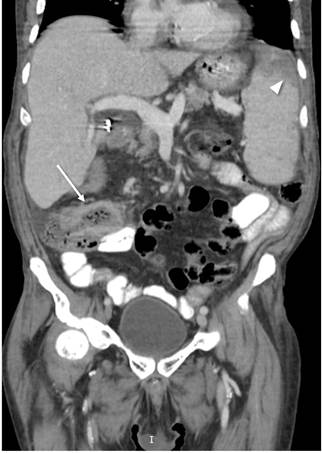

Ante la persistencia de picos febriles con la clínica del paciente, se decidió realizar el cubrimiento antibiótico con cefepima, con un posterior estudio de baciloscopias seriadas negativas. Debido a la alteración de las líneas celulares hematológicas, se ampliaron los estudios con frotis de sangre periférica normal, electroforesis de proteínas con un componente policlonal, citometría de flujo negativa para hemoglobinuria paroxística nocturna y biopsia de la médula ósea negativa para malignidad, con una hipocelularidad del 10 %, esperada para la edad. Se descartó un compromiso medular y se inició el aporte de hierro intravenoso. En el estudio de síndrome febril, estudios adicionales resultaron con un perfil hepático normal, ecografía de abdomen con hallazgos de hepatomegalia y esplenomegalia con múltiples lesiones focales correspondientes a infartos, hemocultivos negativos, antígenos febriles negativos, cultivo de esputo negativo, antígeno prostático normal y ecografía de tiroides sin alteraciones. Se ampliaron los estudios con tomografía de abdomen contrastado con un único hallazgo de engrosamiento de la mucosa ileocecal y las lesiones esplénicas ya documentadas (Figura 3). Se descartó una endocarditis por ecocardiograma transesofágico.